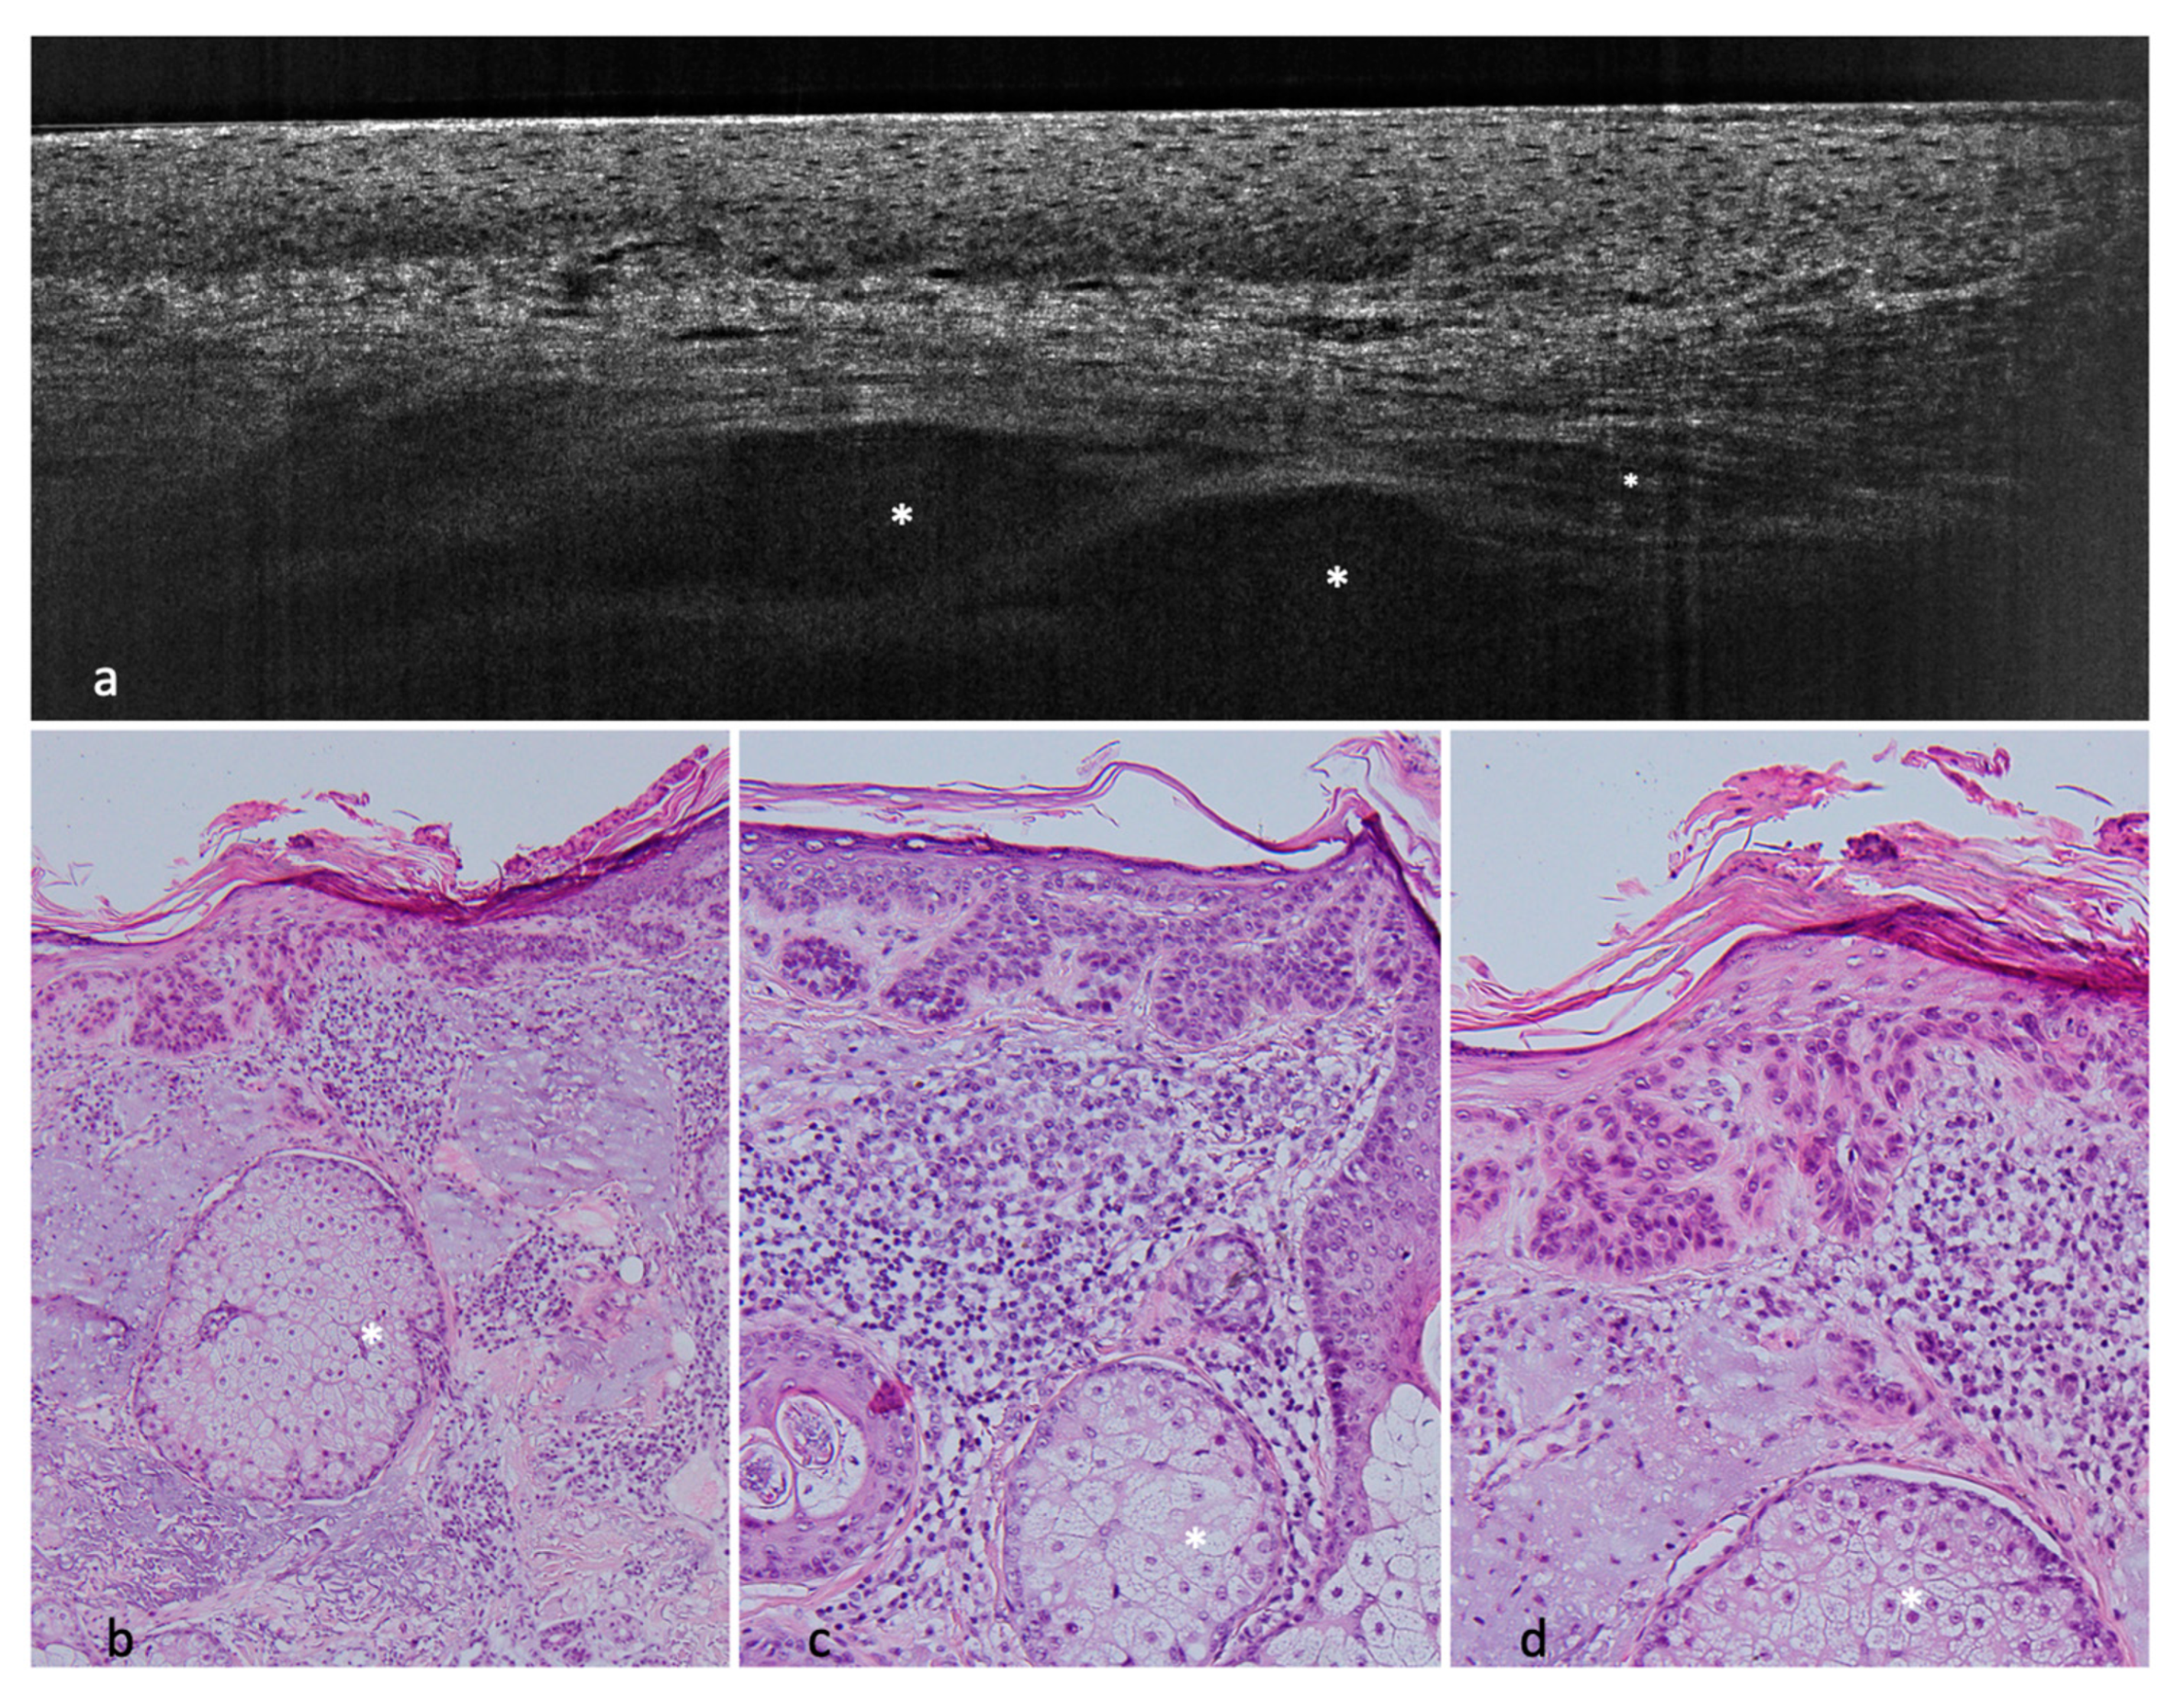

Figure 3. Nodular BCC on the right temple of a 64-year-old male patient. (a) (20×) and (b) (100×): histological HE-stained sections of the tumor. (c) (vertical) and (d) (horizontal): LC-OCT images of the corresponding lesion. Again, peripheral clefting can be seen (white arrow) as well as basaloid nests (asterisks).